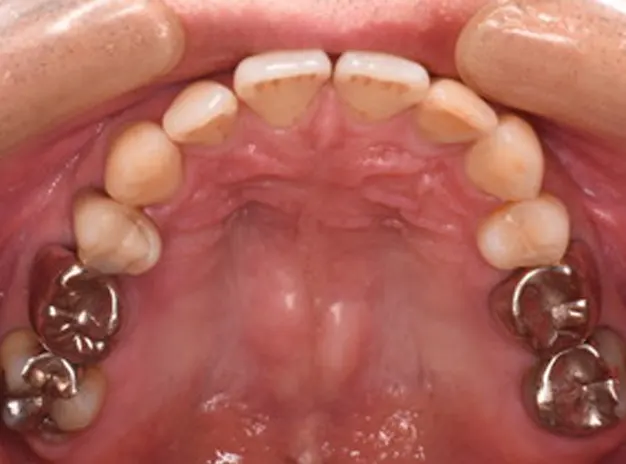

40歳男性

全身の痒みと金属の除去

上顎両側奥歯部

6ヵ月

仮歯:6,000円×4本

ファイバーコア:5,500円×3本

オールセラミッククラウン(奥歯):110,000円×4本

ポーセレンインレー:1本

合計:546,500円(税込)

以前より全身に痒みを訴え、口腔外科より金属アレルギーの改善のため大桑歯科受診を勧められて来院。口腔外バキュームやラバーダム防湿で銀歯撤去時に金属片が飛散しないようにコントロールしながらメタルを撤去し仮歯へ置き換えました。金属がお口から少なくなるにつれて体調が良く痒みもずいぶん少なくなってき様子でした。将来の再治療をなくすためにも、丈夫で長持ちするジルコニアにて最終的な被せ物を作成しました。セラミック治療後は体の痒みや発赤がなくなり、人生が変わったようだと非常に喜んでおられました。